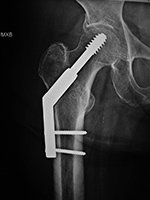

A special type of screw used in the treatment

of intertrochanteric proximal femur fractures

is called a dynamic compression screw (device) consisting of a large lag screw with

distal threads that is inserted into the femoral

head and neck. This screw fits into the barrel of a

side plate, which is secured to the femoral shaft

with multiple cortical screws. The lag screw can

slide within the barrel, which results in compression

of the fracture site as the patient ambulates (figure: hip dynamic compression screw)

(Ruedi, 2007; Benjamin, 1994; Berquist, 1995; Freiberg, 2001; Hunter, 2001). If the fracture settles, the lag screw slides within the barrel preventing the screw from piercing the femoral head and entering the hip joint space.

| Dynamic compression hip screw |

Dynamic compression hip screw, partially threaded cannulated cancellous fixation screw and washer |

Dynamic compression hip screw

|

| There is also a partially threaded cannulated cancellous fixation screw. |